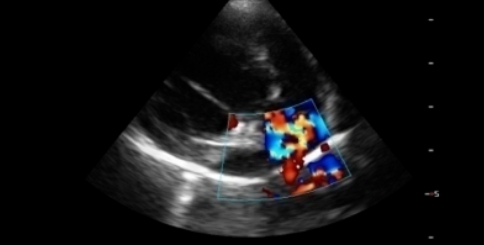

초음파 검사

복부/심장 초음파 검사는 복강 내에 존재하는

장기들은 물론 혈관과 같은 작은 구조물,

심장의 움직임 및 구조까지 실시간으로

평가할 수 있는 비침습적인 검사입니다.

심장 초음파

이럴 때 필요해요.

호흡곤란, 운동 불내성, 기절과 같은 임상증상을

보이는 경우

심장초음파 검사가 필요 할 수 있습니다.

동맥관개존증

이첨판폐쇄부전

심장사상충증